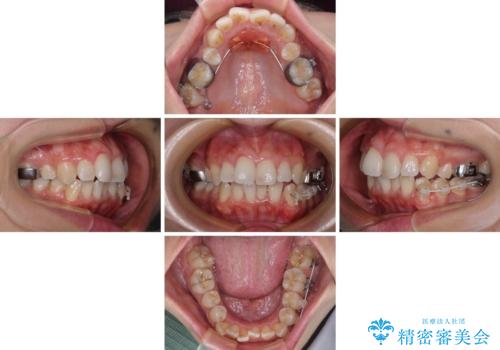

前歯のデコボコを改善 インビザラインの矯正治療

上下顎ともに歯列全体の後方移動とIPR(歯と歯の間を削る)によってデコボコが解消するように設計し、インビザラインにより治療を行うこととしました。

下顎前歯は後戻りを起こしやすいため、舌側を細いワイヤーで固定し、マウスピース型リテーナーで保定を行うこととしました。